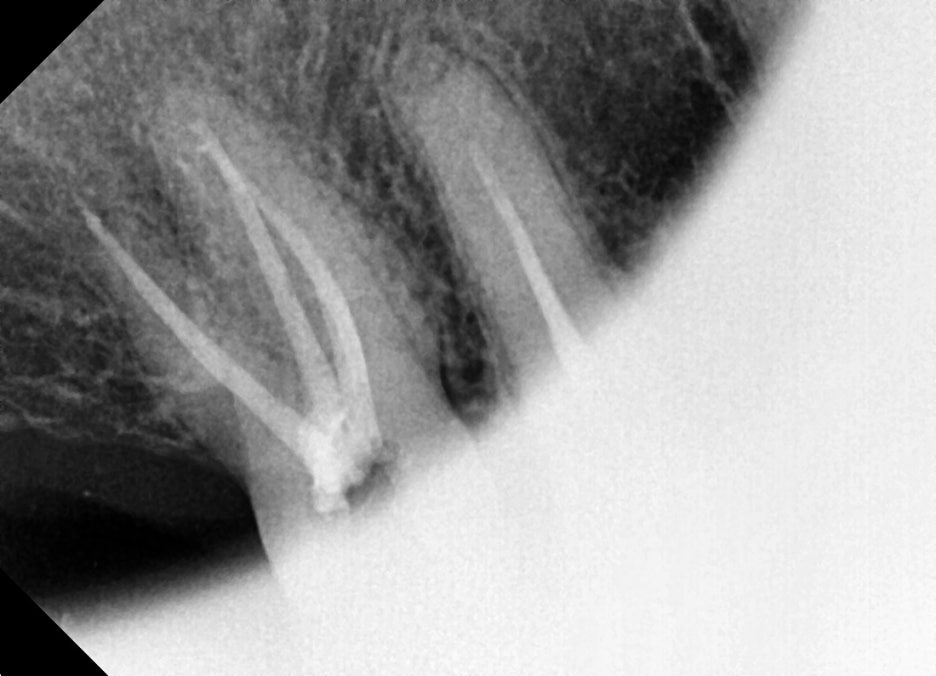

Third root canal treatment – Root canal obturation and core build-up

At the third visit, the space inside the canal is filled with sealer

to block bacteria from invading again.

Once this stage is completed, the root canal treatment is finished.

This prepares the molar to function for chewing again.